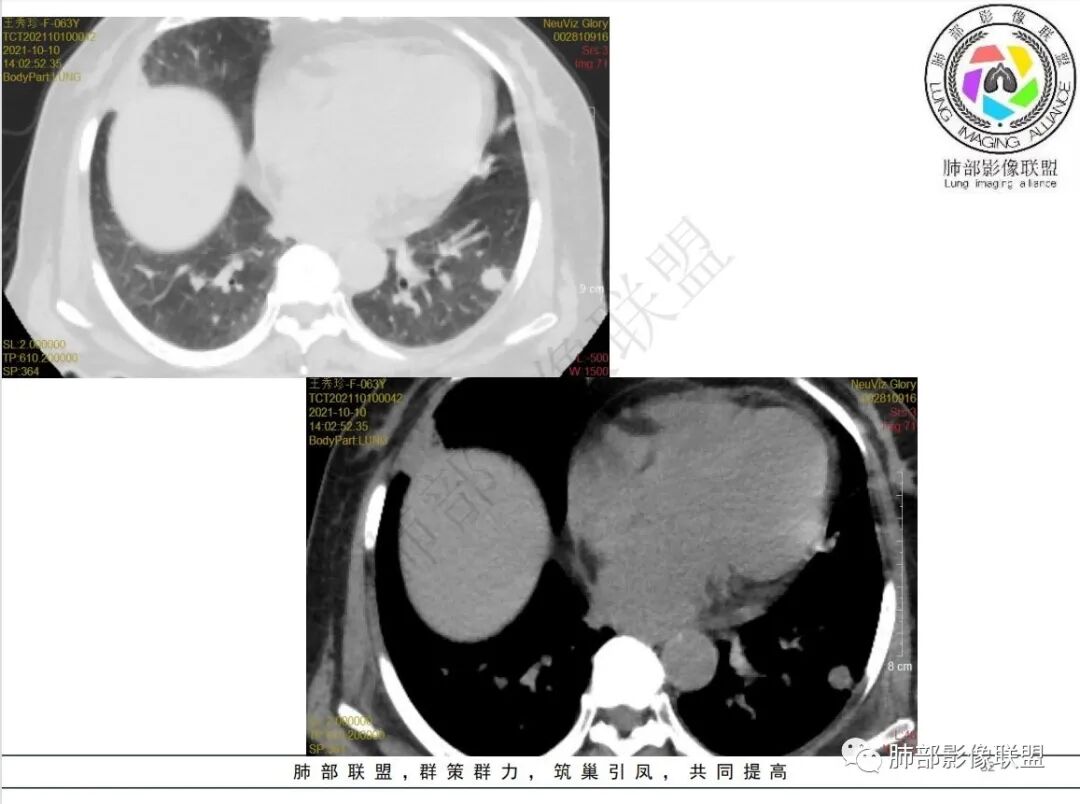

抗真菌治疗1月后复查

4.白血病化疗后,CT上出现多发结节,边缘可见晕征,病灶内可见多发坏死,右肺中叶肺动脉可见充盈缺损,右肺中叶可见融冰征,右肺中叶肺动脉侵犯栓塞伴右肺中叶肺梗死,可符合真菌感染。

6.肺曲霉病典型的CT表现是结节周围有磨玻璃样的晕征表现,或胸膜为宽基底的楔形实变。晕征表现为曲菌感染的肺结节伴梗死和凝固性坏死,周围有肺泡出血。最终可出现空泡征象,并可观察到中央坏死组织与周围肺实质分离形成空气新月征。

晕征已被认为是侵袭性曲菌病的早期征象之一。